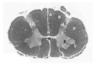

Which pathway runs through the region indicated by the asterisk?

- Lateral lemniscus

- Spinothalamic tract

- Vestibulospinal tract

- Corticospinal tractt

- Spinocerebellar tract

Which pathway runs through the region indicated by the asterisk?

- Lateral lemniscus

- Spinothalamic tract

- Vestibulospinal tract

* *4. Corticospinal tractt** - Spinocerebellar tract